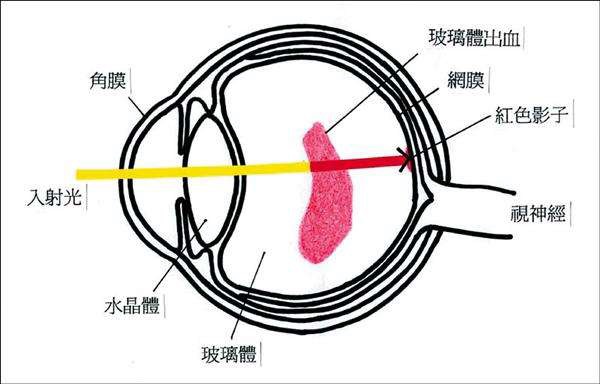

A:飛蠅症又稱飛蚊症和玻璃體混濁,是指玻璃體內出現不透明體,造成患者視物出現模糊。人出生時玻璃體呈凝膠狀態,是重要的屈光介質,正常的玻璃體隨著年齡逐漸出現液化,從而導致玻璃體混濁。此外,一切玻璃體混濁是由於病理原因所導致,例如玻璃體出血、葡萄……

A:眼前出現飛蚊的症狀往往是因為玻璃體發生了液化、變性和混濁,通常情況下玻璃體的混濁,比較多見於近視眼的人和年歲比較大的中老年人,還要特別重視的一個問題是當眼底有病變發生的時候,也會出現玻璃體的混濁、玻璃體混濁的加重,這時候眼前飛蚊的症狀需要做……

A:年輕人飛蚊症可由以下常見原因所導致:1、高度近視:通常是指600度以上的近視,在近視的發展過程中玻璃體會逐漸液化,從而表現為飛蚊症。如果除了有飛蚊症的感覺,還伴有眼前的異常散光感,或者短時間內飛蚊不斷增加,年輕人需要到醫院進行眼底檢查,防……

A:年輕人眼睛出現飛蚊症,根據病因不同治療也有所不同,常見病因如下:1、高度近視所引起:通常是指600度以上的近視,在近視的發展過程中,玻璃體逐漸液化出現飛蚊症。如果僅有飛蚊症的感覺,通常不需要進行特殊的治療,但是需要去醫院進行定期檢查,防止……

A:眼睛裡有飛蚊的現象主要是因為玻璃體發生了液化、變性和混濁,玻璃體原本在眼睛裡邊是一個膠凍狀的結構,由於近視眼以及中高度近視或者年齡過大了,中老年人就會出現玻璃體的液化、變性和混濁,這種情況下很難通過任何治療,將已經液化的玻璃體恢復到膠凍狀的……